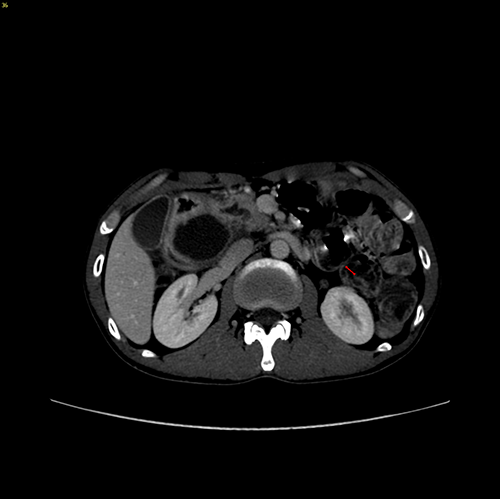

慢性胰腺炎伴假性囊肿形成